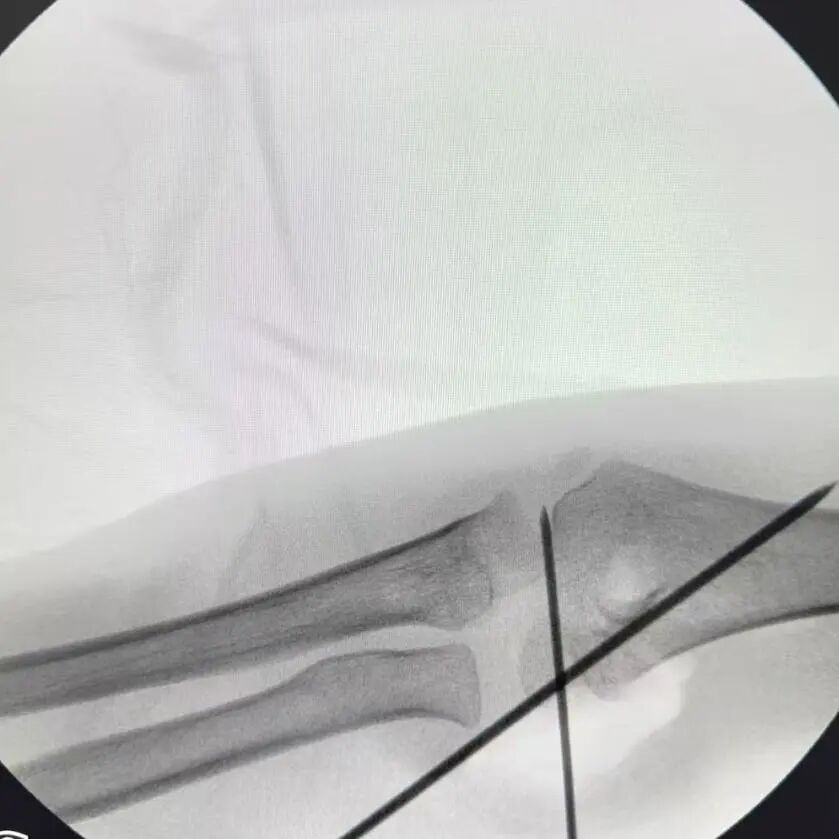

同样“抢时间”的还有小罗和小周的治疗:4岁小罗9月15日深夜入院,10小时后顺利手术;7岁小周同一晚受伤,也在10小时内完成肱骨髁上骨折闭合复位经皮固定术。6岁小郑更是创下“4小时极速手术”纪录——早晨7点40分受伤,8点多入院,11点多手术结束,当天下午就能躺上网课。

“我们的目标是‘24小时内完成急诊手术’,尽量让孩子少耽误一节课。”骨伤科手外·儿骨·烧伤整形组主任陈孝均教授介绍,为了实现这个目标,团队制定了专属流程:孩子入院后,急诊优先开具检查单,放射影像科快速出片;骨科医生同步评估病情,确定手术方案;麻醉科提前做好准备,只要术前检查合格,立刻安排手术——哪怕是深夜或周末,团队也随时待命。